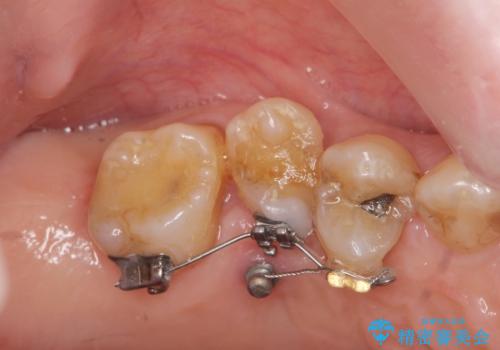

部分矯正を含む 歯周病治療 (再生治療・歯周ポケット除去・MTM・連結補綴)

検査の結果、強い歯ぎしりによる歯の周囲の骨の吸収が認められたため歯槽骨の再生・歯周ポケットの除去・力に対抗する連結補綴・補綴前処置としての小矯正を計画します。

今回連結補綴を行うにあたり、歯周病の問題を解決するために再生療法・歯周ポケット除去手術を、またより歯の神経を保存し力に対抗できる環境を整えるために小矯正を行い精度の高いメタルボンドクラウンを製作することができました。